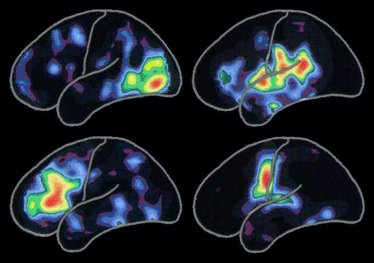

7. La codification des signaux

100 milliards de cellules nerveuses… 100 trillions de synapses…. des douzaines de neurotransmetteurs… C'est cette « force du nombre » qui fournit au cerveau sa matière première. Avec le temps, les expériences accumulées créent des schémas correspondant à différents types et intensités de signaux. Ces schémas d'activité expliquent comment notre cerveau code, au niveau de la cellule, nos pensées, nos souvenirs, nos aptitudes et notre identité.

La tomographie par émission de positrons (TEP) ci-contre montre les schémas normaux d’activité cérébrale activés lorsque:

L’activité est plus intense dans les zones rouges et les autres couleurs de l’arc-en-ciel, du jaune au bleu violacé, indiquent une diminution progressive de cette activité.

Les schémas associés à une activité spécifique évoluent tout au long de notre vie, au fil des nouvelles rencontres et expériences et de l’acquisition de nouvelles aptitudes. Les schémas changent aussi lorsque la maladie d’Alzheimer ou un trouble apparenté perturbe les cellules nerveuses et les connexions entre elles.